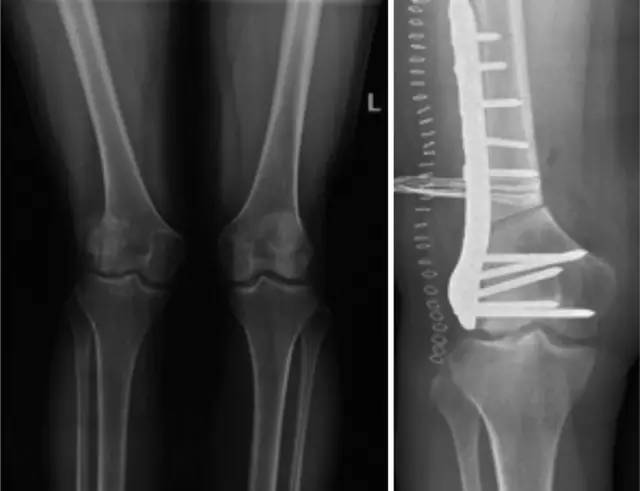

各种晚期骨关节病的关节置换手术治疗是北京清华长庚医院关节外科中心的一大特色,包括股骨头坏死、髋膝骨关节炎、类风湿关节炎、强直性脊柱炎、髋关节发育不良、关节强直、超过80岁的超高龄股骨颈骨折患者的关节置换手术等,我中心在人工关节初次置换及翻修上作了大量工作,置换的难度和手术效果方面已达到国际先进水平,导航下全膝关节置换术:大大提高膝关节置换手术的精确度。

局限性关节置换手术(UKA)

全膝关节表面置换手术(TKA)

铰链式人工膝关节置换手术(HK)膝关节周围韧带严重破坏

国内首例膝关节置换术后Felix IIB型胫骨假体周围骨折翻修术

胫骨截骨矫形手术(HTO)

股骨远端截骨矫正膝外翻